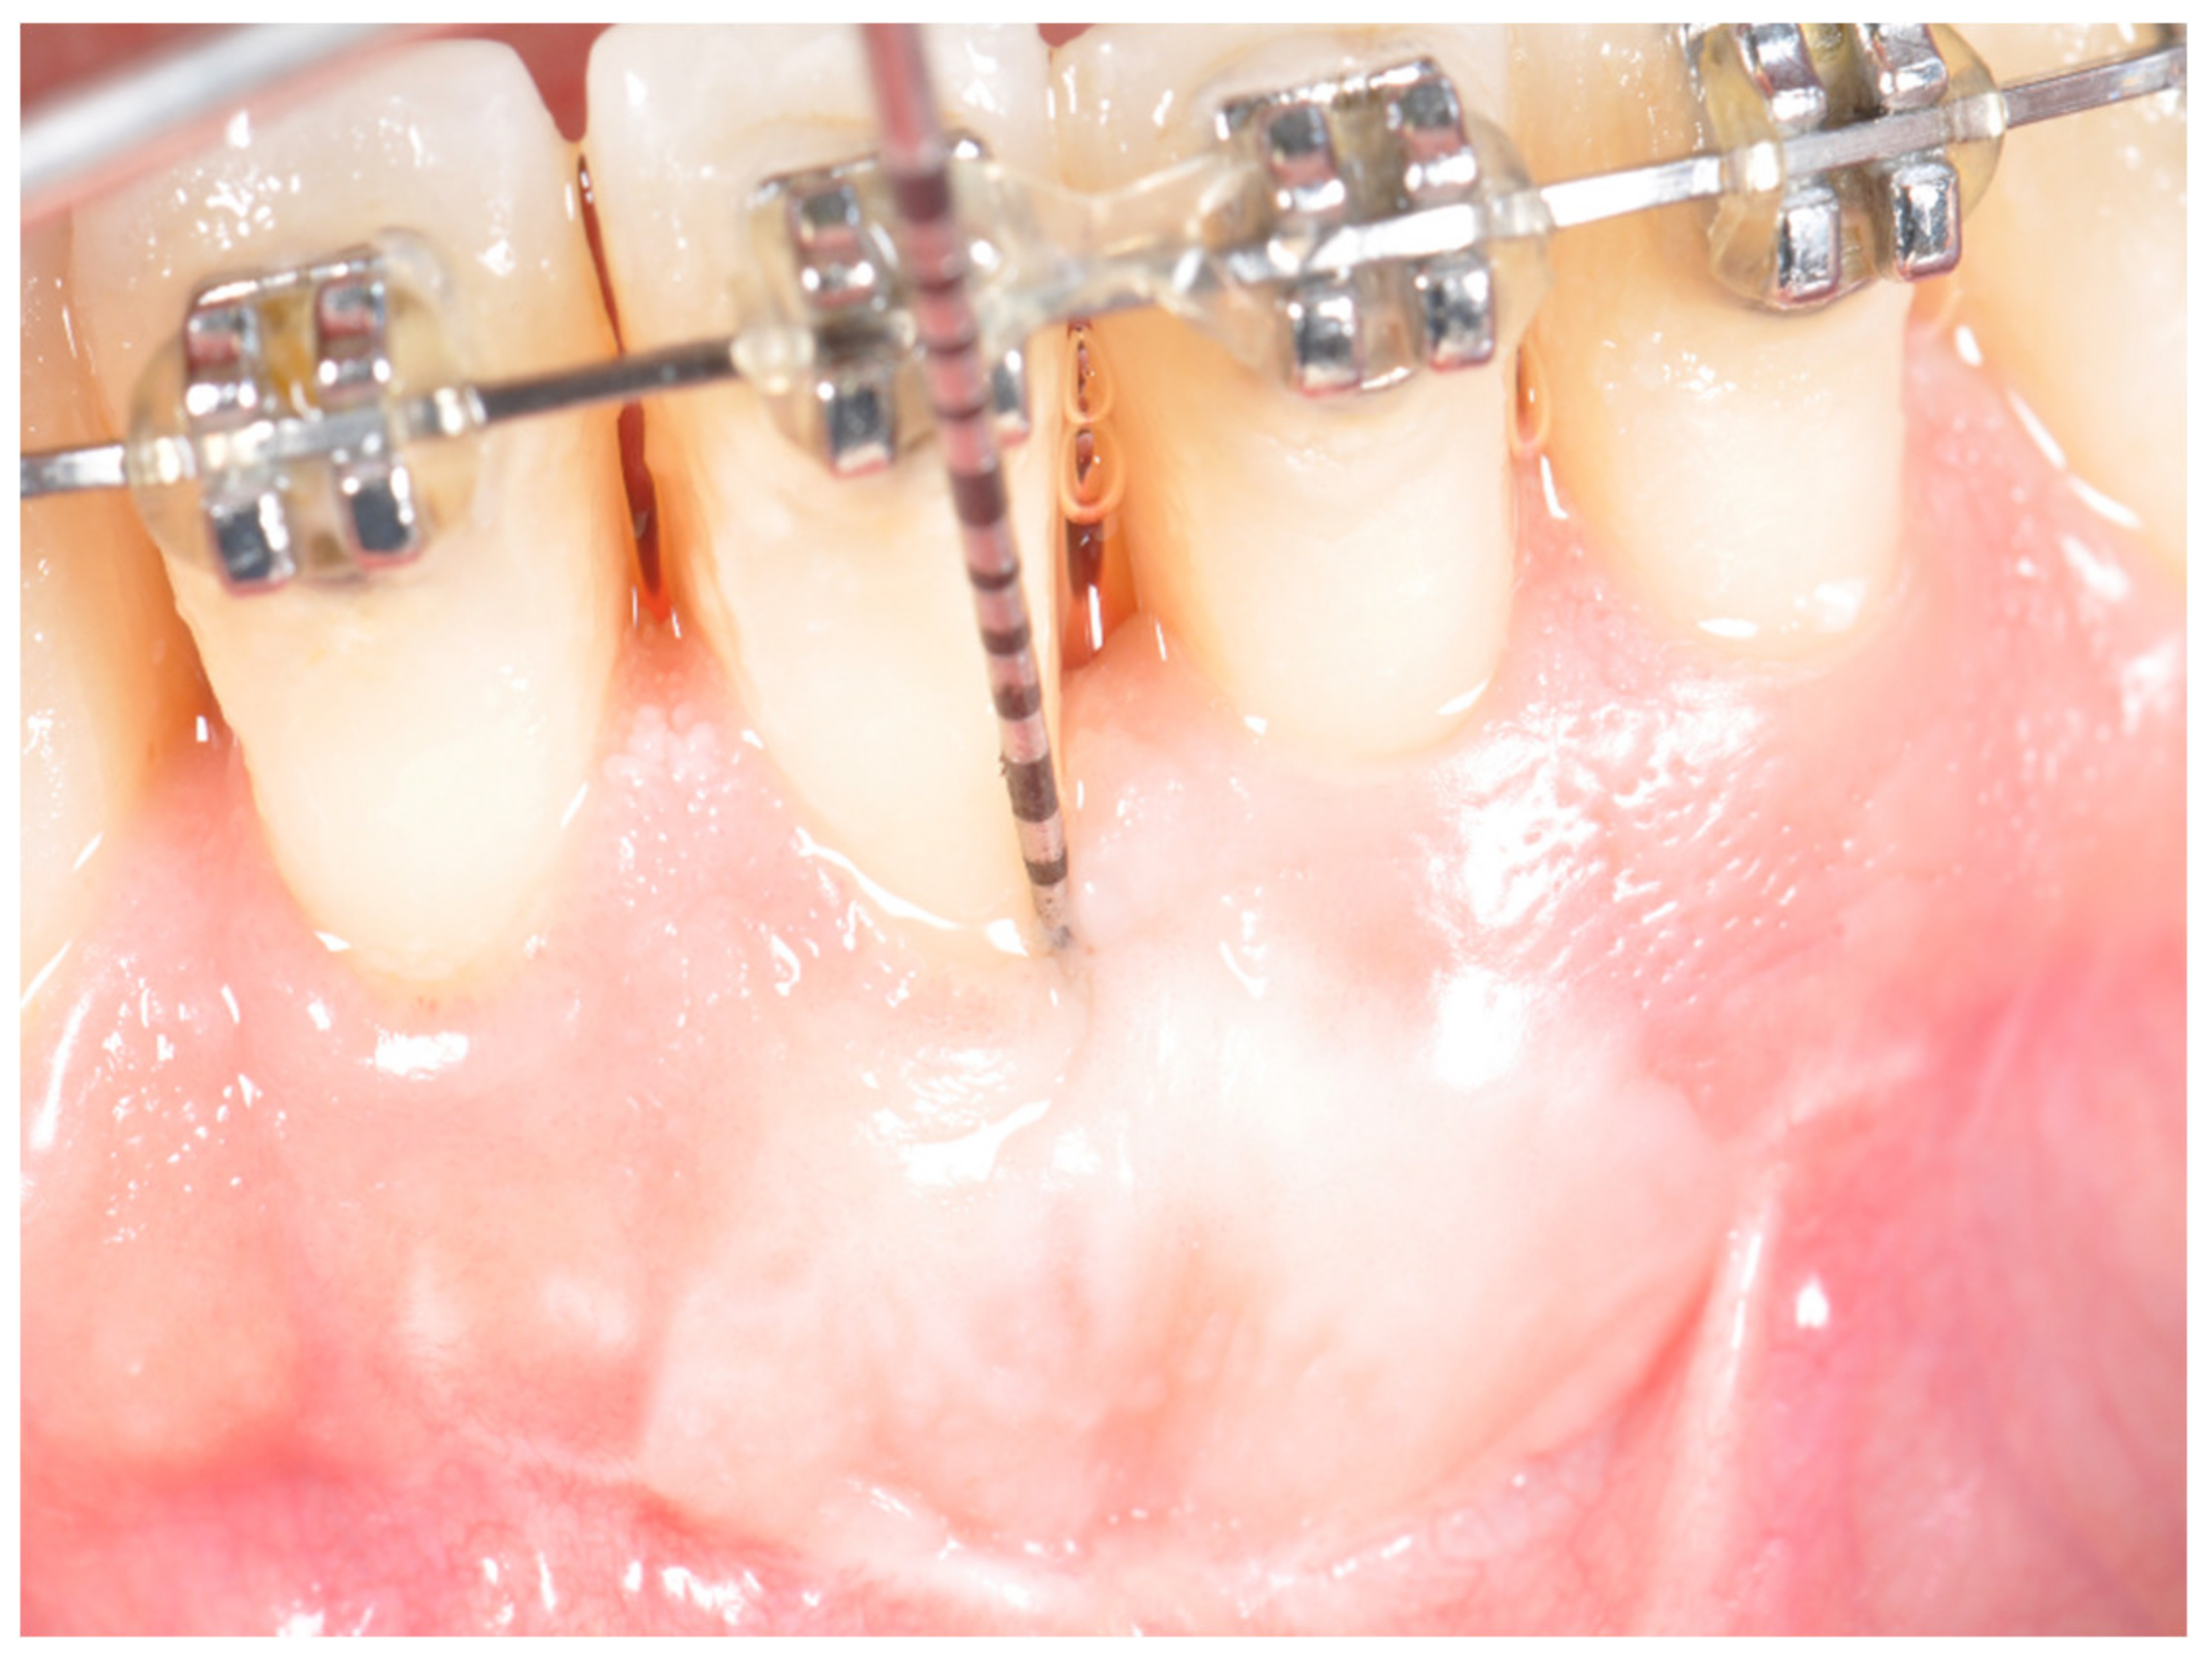

2. Materials and Methods

- The graft was measured with the probe and its measurements recorded;